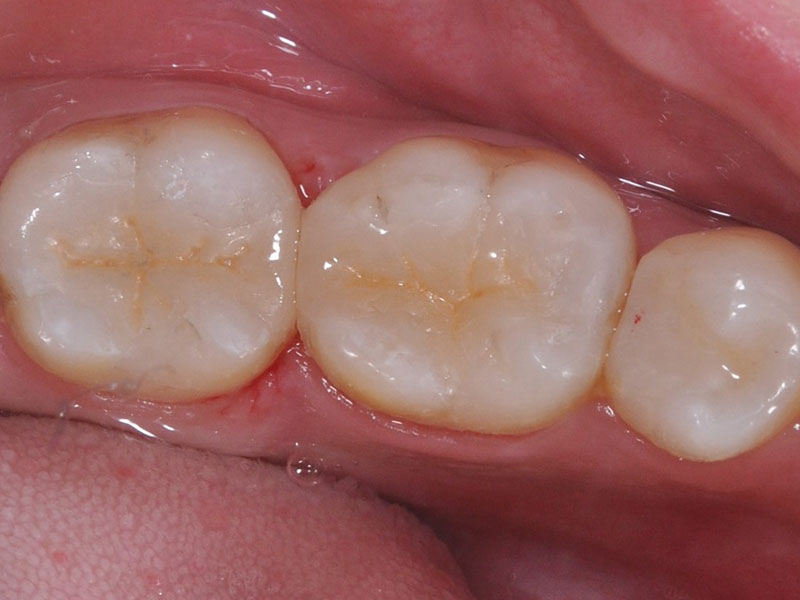

治療後